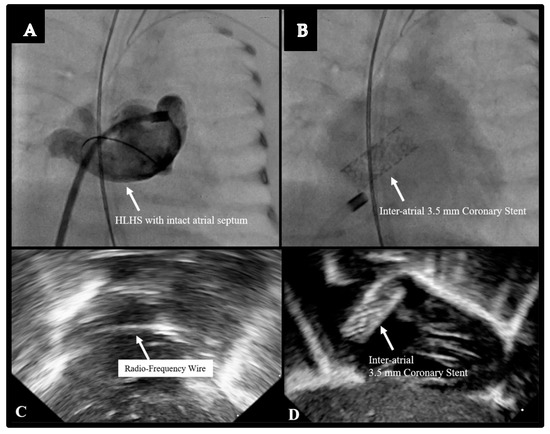

| 10. Radiofrequency perforation for HLHS with intact atrial septum with inter-atrial stent placement | 1 |

| 10. Radiofrequency perforation for HLHS with intact atrial septum with inter-atrial stent placement † | 1 | 0 | 0 | 0 |